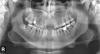

AlexandrN Опубликовано 29 октября, 2009 Поделиться Опубликовано 29 октября, 2009 Здравствуйте! Помогите, пожалуйста, советом.В результате несчастного случая потерял два верхних резца (11 и 21) и два нижних (31 и 41), справа после резцов зуб шатается (12 - удалять однозначно), через один тоже шатается но совсем немного(14 - удалять ?). Сходил на консультацию в поликлинику, сказали гигиеническая чистка, кюретаж, депульпирование, удаление нескольких, обточка под металлокерамику и протезирование (имплантами не занимаются, но и не сказали что противопоказаны). Сходил в стоматологию, пародонтит - сначала гигиеническая чистка, восстановление гигиены (учить чистить по другому, ёршики, ирригатор = порядка месяц), кюретаж, удаление почти всех зубов на верхней и половины на нижней, депульпирование оставшихся, затем по результатам съёмный/несъёмный протез (импланты сказали делать нельзя и точка). Неужели так всё печально, как мне сказали (снимок внизу)?Порекомендуйте возможный план лечения?Почему нельзя делать имплантацию (вроде минимально 6мм)?Можно или нет в период лечения носить съемный протез из нейлона или другой вариант? Территориально в Мурманске, возраст 29 лет.Хронических заболеваний нет. Если можете посоветуйте специалиста в нашем городе, к которому стоило бы обратиться. Ссылка на комментарий